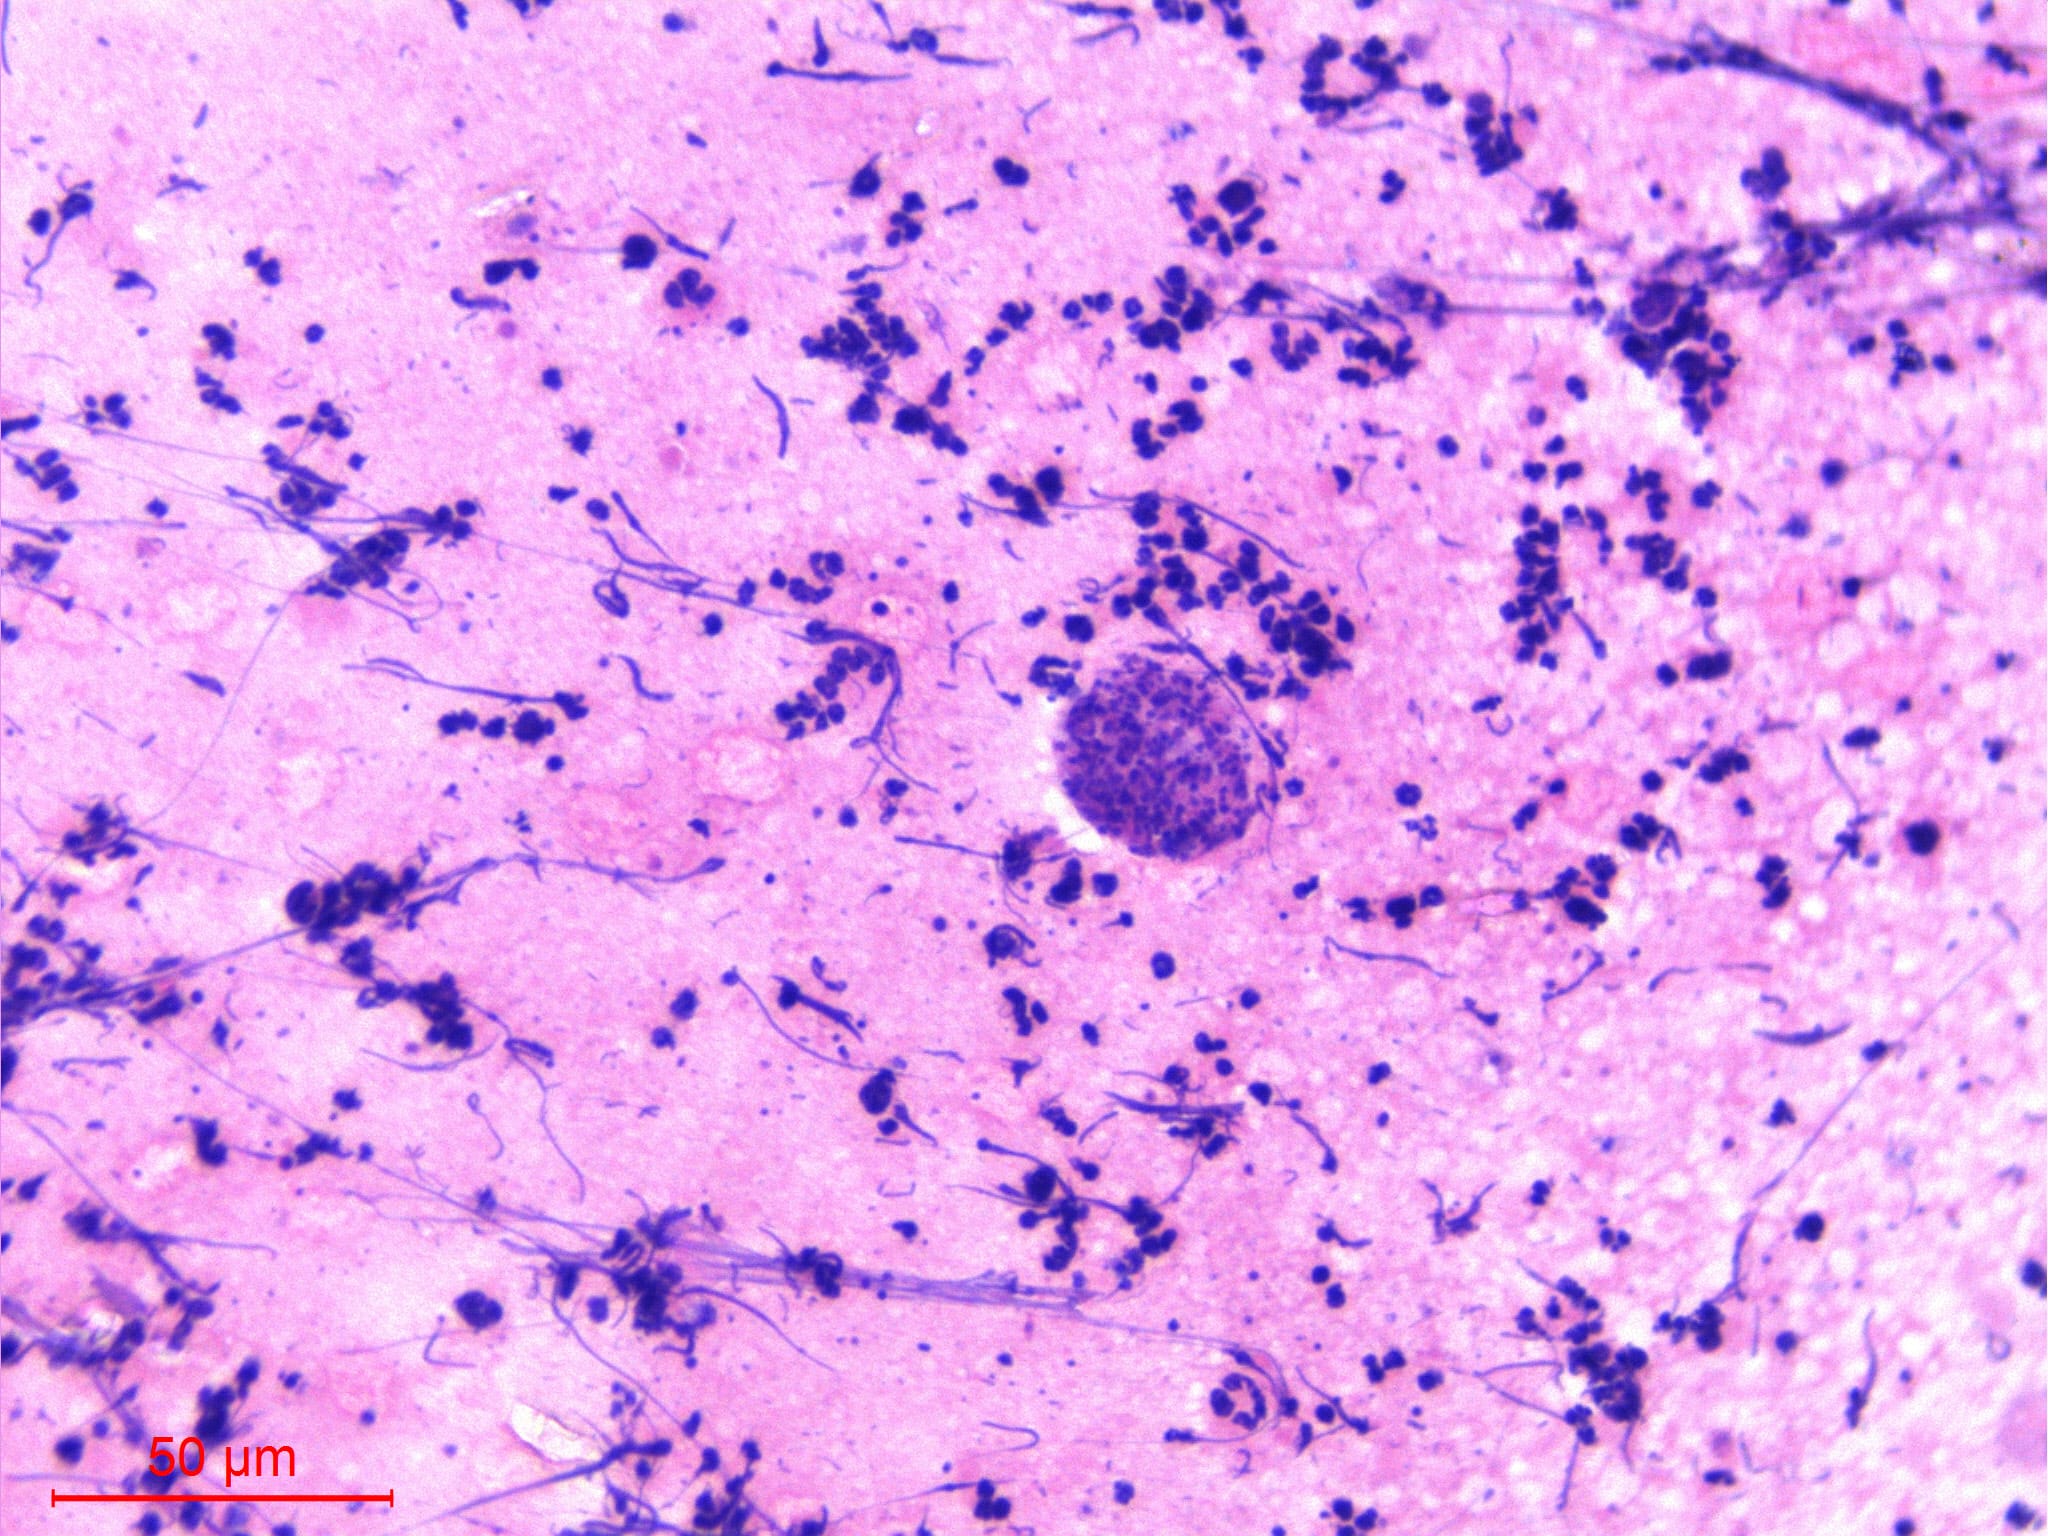

Microscopic (histologic) description

Microscopic (histologic) images

Contributed by Sajna V.M. Kutty, M.D.

- Wuchereria bancrofti accounts for up to 90% of cases

- Diagnosis is typically made by identifying microfilariae in peripheral blood smears

- Rarely, microfilariae are coincidentally detected in FNAC in association with various inflammatory and neoplastic lesions

- Wuchereria bancrofti can be identified by its sheath and multiple, coarse, discrete nuclei extending from head to tail except in the small terminal portion of the caudal end

Microscopic (histologic) description

- Wuchereria bancrofti can be identified by its sheath and multiple, coarse, discrete nuclei extending from head to tail except in the small terminal portion of the caudal end

Microscopic (histologic) images

Contributed by Sajna V.M. Kutty, M.D.